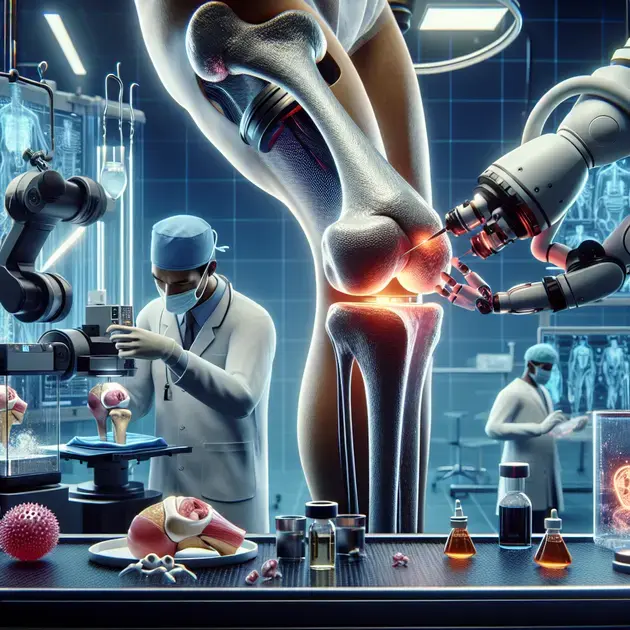

Understanding total knee replacement surgery is essential for those considering the procedure. This surgery is typically recommended for individuals with severe knee arthritis or injuries that have not responded to conservative treatments. Total knee replacement involves removing damaged cartilage and bone from the knee joint and replacing it with an artificial joint made of metal and plastic components.

Another crucial step in understanding total knee replacement surgery is consulting with healthcare providers. Orthopedic surgeons specializing in joint replacement can offer valuable insights into the procedure, answer any questions or concerns, and provide personalized recommendations based on individual health conditions.

Engaging in physical therapy and rehabilitation exercises is essential for restoring knee joint function and strength. Physical therapists will create personalized exercise programs to improve mobility, flexibility, and muscle strength in the operated knee, gradually progressing as the recovery advances.